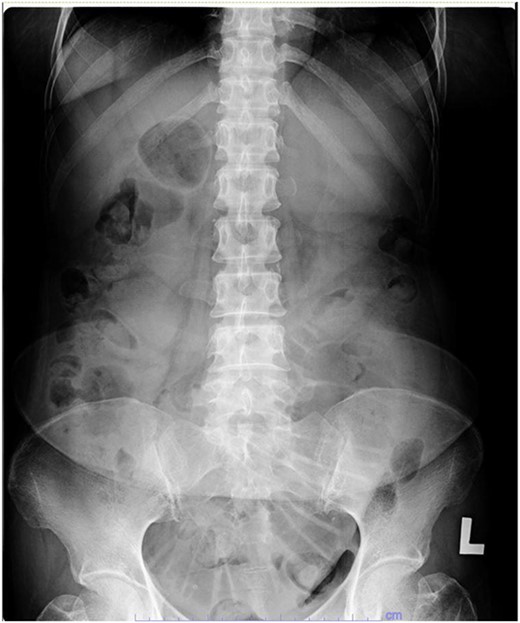

Her abdominal x-ray showed a dilated small bowel with a most likely transition point at the ileum and a collapsed large bowel (Fig. 1). Computed tomography (CT) of the abdomen showed an intussusception with the transition point at the proximal ileum with mesenteric invagination (Figs. 2 and 3).

Coronal view of CT scan. Intussusception transition point is seen likely at the proximal ileum with evidence of ‘bowel in bowel’ appearance, measuring ~7.8 cm.